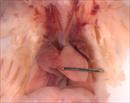

| Mutant 012-029-NB has a cleft lip and polydactyly | Cplane1b2b012Clo/Cplane1b2b012Clo | C57BL/6J-Cplane1b2b012Clo |

| Mutant 012-029-NB has polydactly on all four limbs | Cplane1b2b012Clo/Cplane1b2b012Clo | C57BL/6J-Cplane1b2b012Clo |